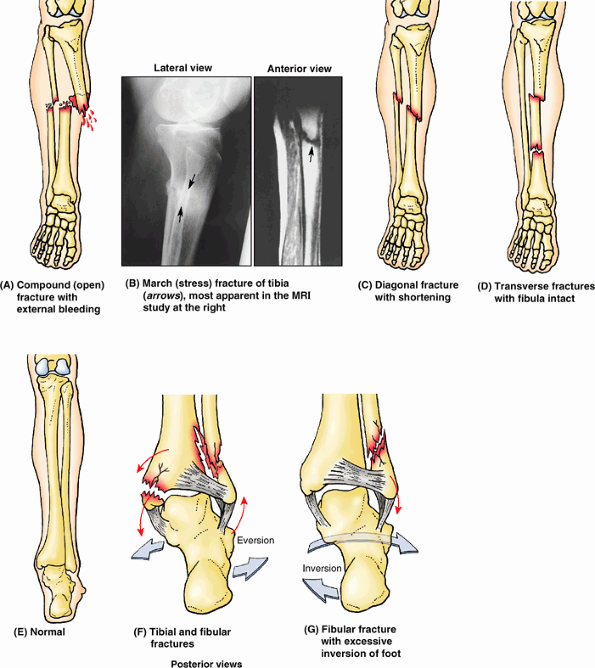

middle and inferior thirds, which is the most frequent site of

fracture. Unfortunately, this area of the bone also has the poorest

blood supply. Because its anterior surface is subcutaneous, the tibial

shaft is the most common site for a compound fracture (Fig. B5.4A).

Compound tibial fractures may also result from direct trauma (e.g., a

“bumper fracture” caused when a car bumper strikes the leg). Fracture

of the tibia through the nutrient canal predisposes the patient to

non-union of the bone fragments resulting from damage to the nutrient

artery.

are common in people who take long hikes before they are conditioned

for this activity. The strain may fracture the anterior cortex of the

tibia. Indirect violence applied to the tibial shaft when the bone

turns with the foot fixed during a fall may produce a fracture (e.g.,

when a person is tackled in football). In addition, severe torsion

during skiing may produce a diagonal fracture (Fig. B5.4C) of the tibial shaft at the junction of the middle and inferior thirds as well as a fracture of the fibula.

Diagonal fractures are often associated with limb shortening caused by

overriding of the fractured ends. Frequently during skiing, a fracture

results from a high-speed forward fall, which angles the leg over the

rigid ski boot, producing a “boot-top fracture” (Fig. B5.4D).

When a person slips and the foot is forced into an excessively inverted

position, the ankle ligaments tear, forcibly tilting the talus against

the lateral malleolus and shearing it off (Fig. B5.4G). Fractures of the lateral and medial malleoli

are relatively common in soccer and basketball players. Fibular

fractures can be painful owing to disrupted muscle attachments; walking

is compromised because of the bone’s role in ankle stability.

Figure B5.4